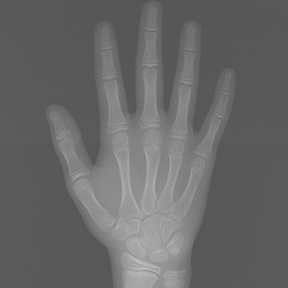

얼굴 골격의 성장에 문제가 있는지를 파악하기 위한 적절한 시기는 초등학교 입학 전인 6-7세경입니다. 이때는 유치에서 영구치로 교환되는 시기로서 부정교합 여부가 결정되는 중요한 시기이므로 이 시기를 잘 관찰하여 부정교합을 예방하는 것 또한 중요합니다. 교정의 정확한 시기는 6개월 간격으로 치과에 정기적으로 내원하여 성장 분석을 받은 후 결정하는 것이 좋습니다.